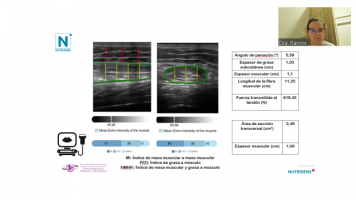

“Obesidad sarcopénica, una entidad emergente”. 40 minutos.

“Caso clínico: Tratando a un paciente con Obesidad sarcopénica”. 20 minutos